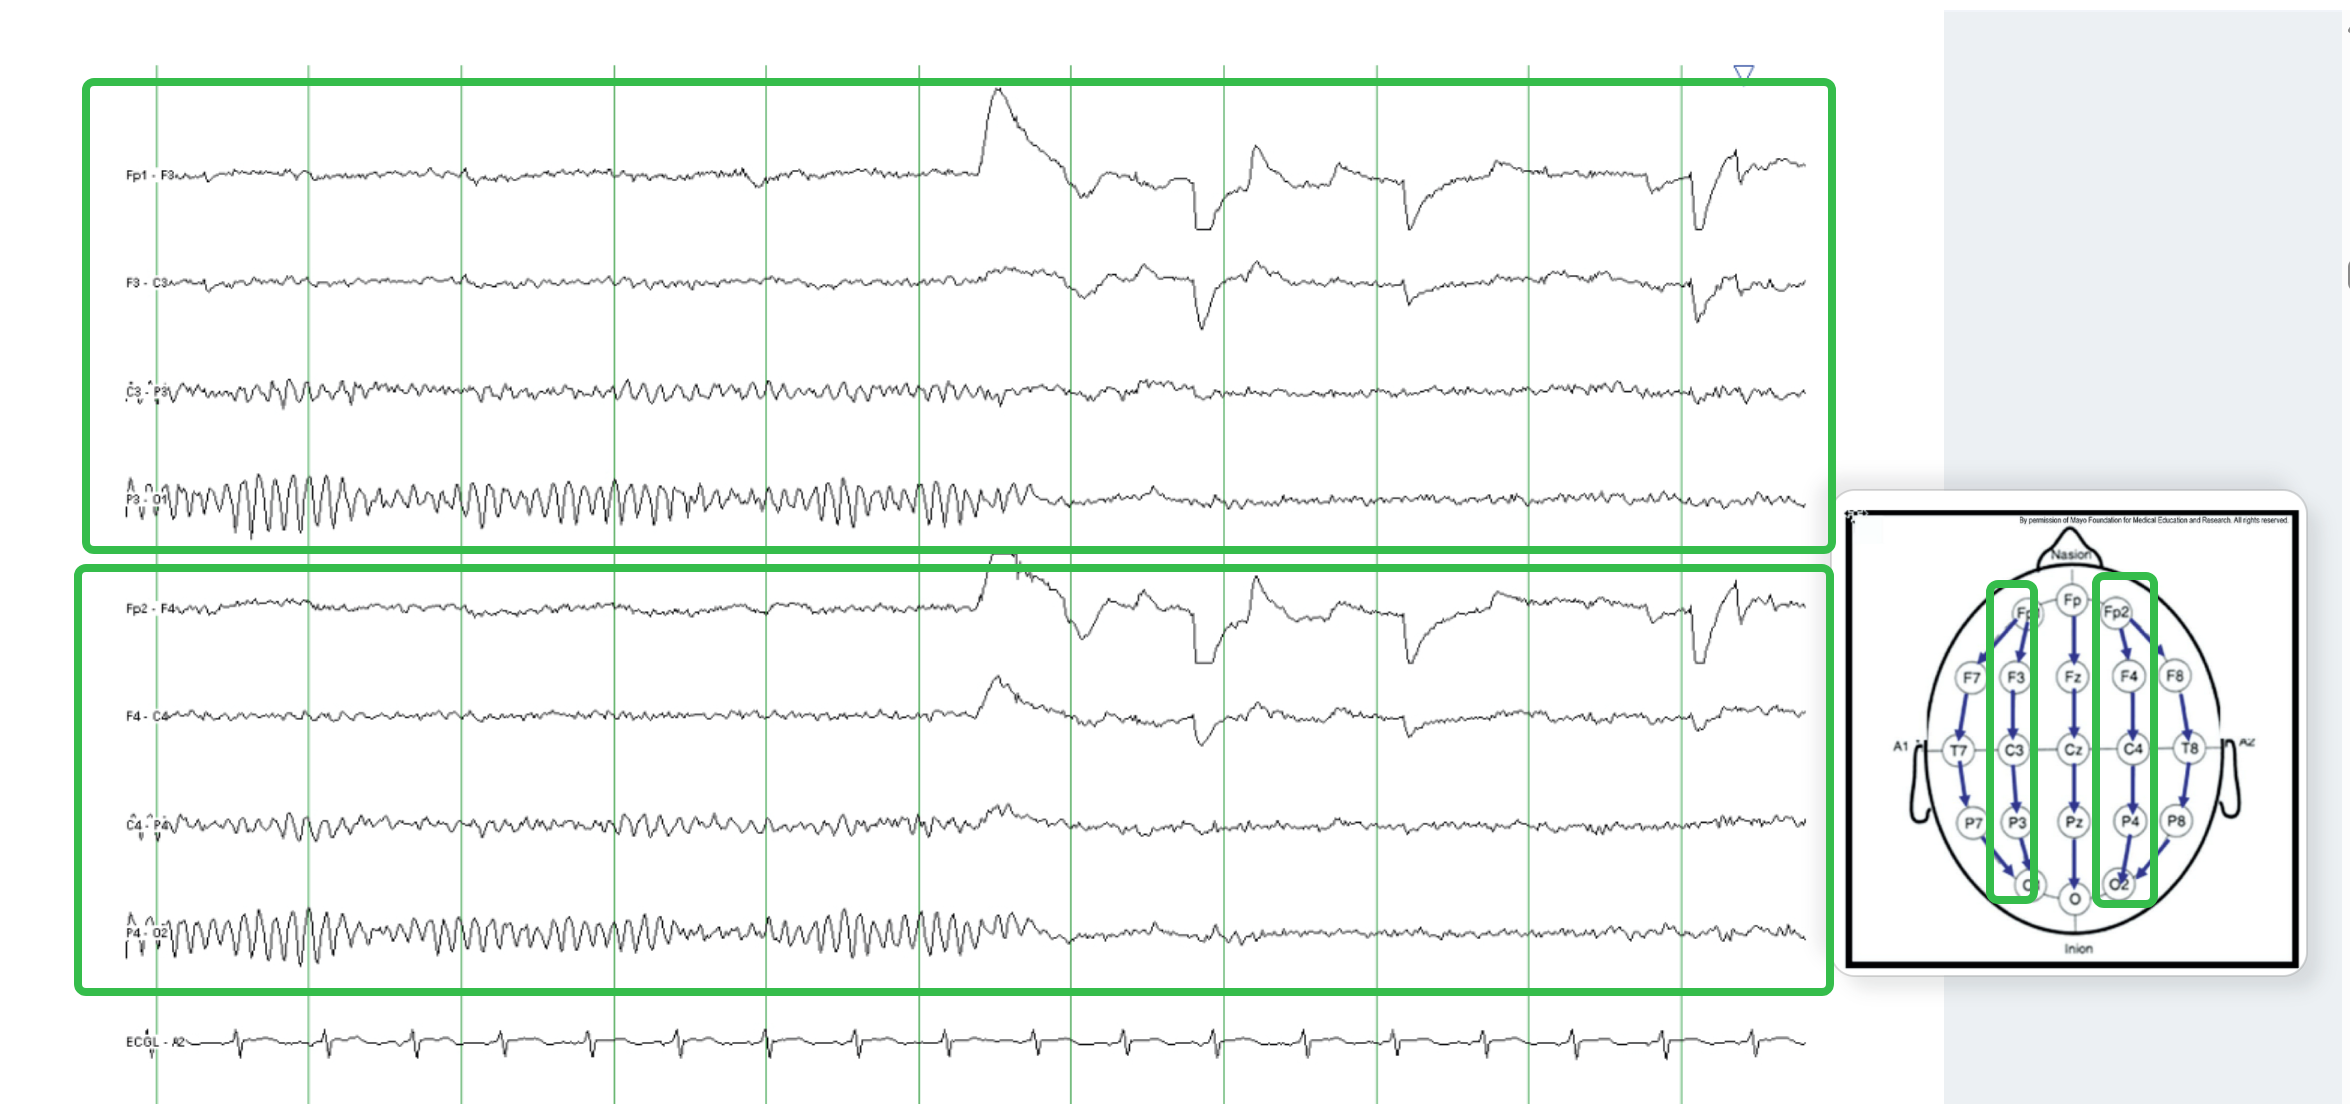

在这里插入图片描述

2. 电极的命名与分布

每个电极位点用 一个字母一个给定的数字 表示。

• 字母代表脑叶:

- F(额叶)、T(颞叶)、P(顶叶)、O(枕叶)

• 奇数代表左侧,偶数代表右侧,中线用“z”表示。

• 例如:F3 位于左额叶,O2 位于右枕叶